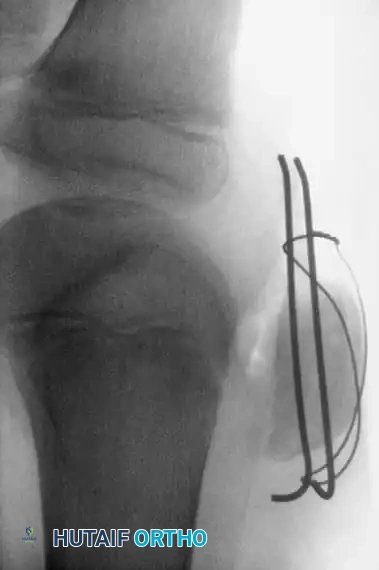

4. Internal Fixation (Tension Band Principle)

* Drive two parallel, longitudinal Steinmann pins (or heavy Kirschner wires) from distal to proximal across the fracture site.

* Leave the pins protruding approximately 0.5 cm (1/4 inch) distally to facilitate future removal.

* Pass a flexible stainless-steel wire (18- or 20-gauge, depending on patient size) transversely through the insertion of the quadriceps tendon at the superior pole.

* Pass the wire distally, crossing it in a figure-of-eight fashion over the anterior surface of the patella.

* Pass the wire deep to the protruding Steinmann pins at the inferior pole.

- Tighten the tension band wire symmetrically. The tension band converts the tensile forces of the quadriceps into compressive forces at the articular surface during knee flexion.

- Pitfall: Do not overtighten the wire, as this can cause anterior gaping and posterior articular angulation of the cartilaginous fragment.